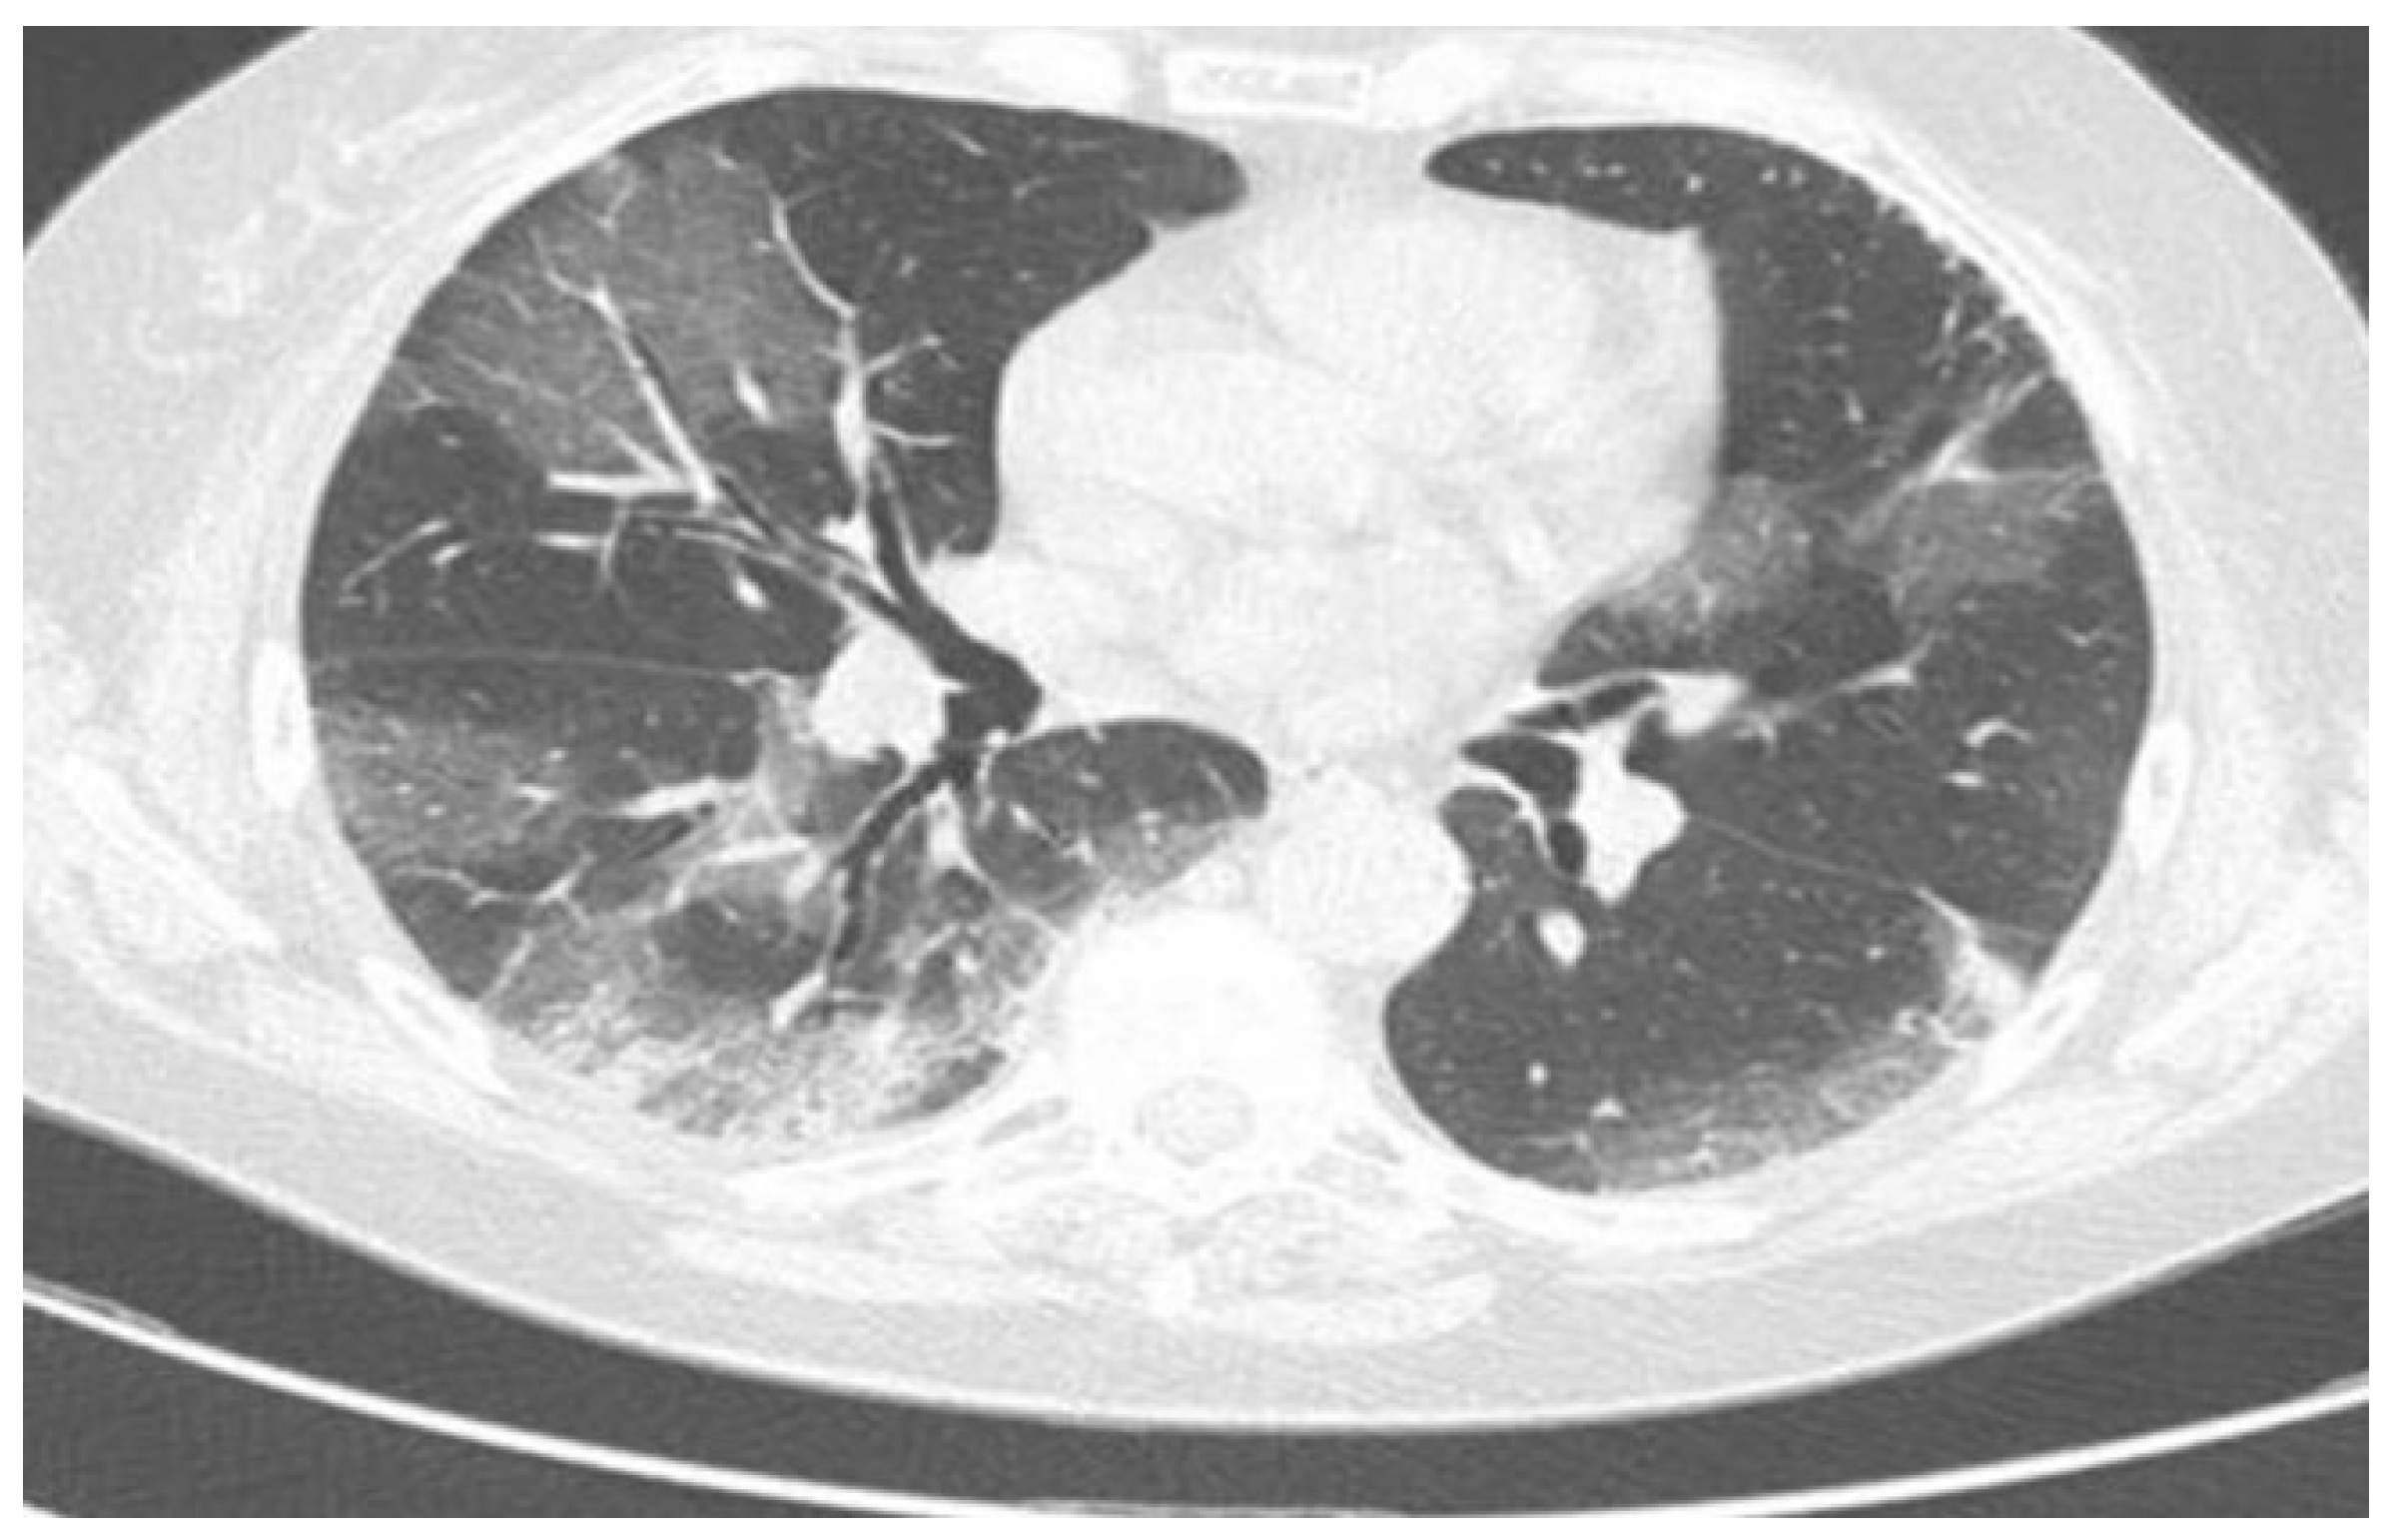

- Brandi, N.; Ciccarese, F.; Rimondi, M.R.; Balacchi, C.; Modolon, C.; Sportoletti, C.; Renzulli, M.; Coppola, F.; Golfieri, R. An Imaging Overview of COVID-19 ARDS in ICU Patients and Its Complications: A Pictorial Review. Diagnostics 2022, 12, 846. [Google Scholar] [CrossRef]